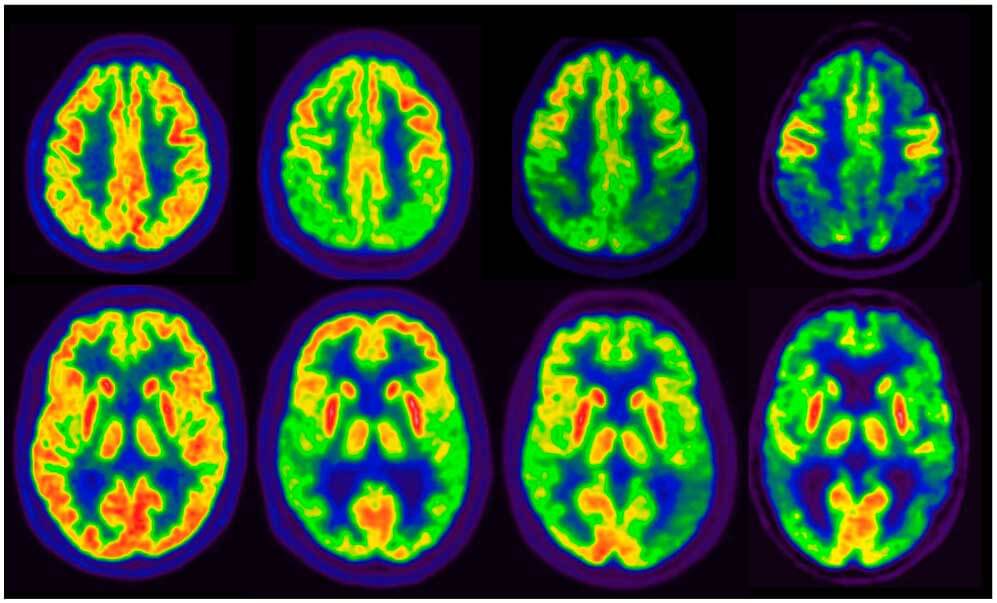

En un estudio observacional de gran tamaño se observó que la tasa de PET cerebral positivo para tau alcanzaba un 10% en individuos sin deterioro cognitivo, y la combinación de positividad para PET de amiloide beta (Aβ) y tau se asoció con un alto riesgo de progresión clínica, tanto en la etapa preclínica como en la sintomática de la enfermedad de Alzheimer. Estos hallazgos subrayan el potencial de la PET para tau como biomarcador para la estadificación de la enfermedad. JAMA, 16 de junio de 2025.